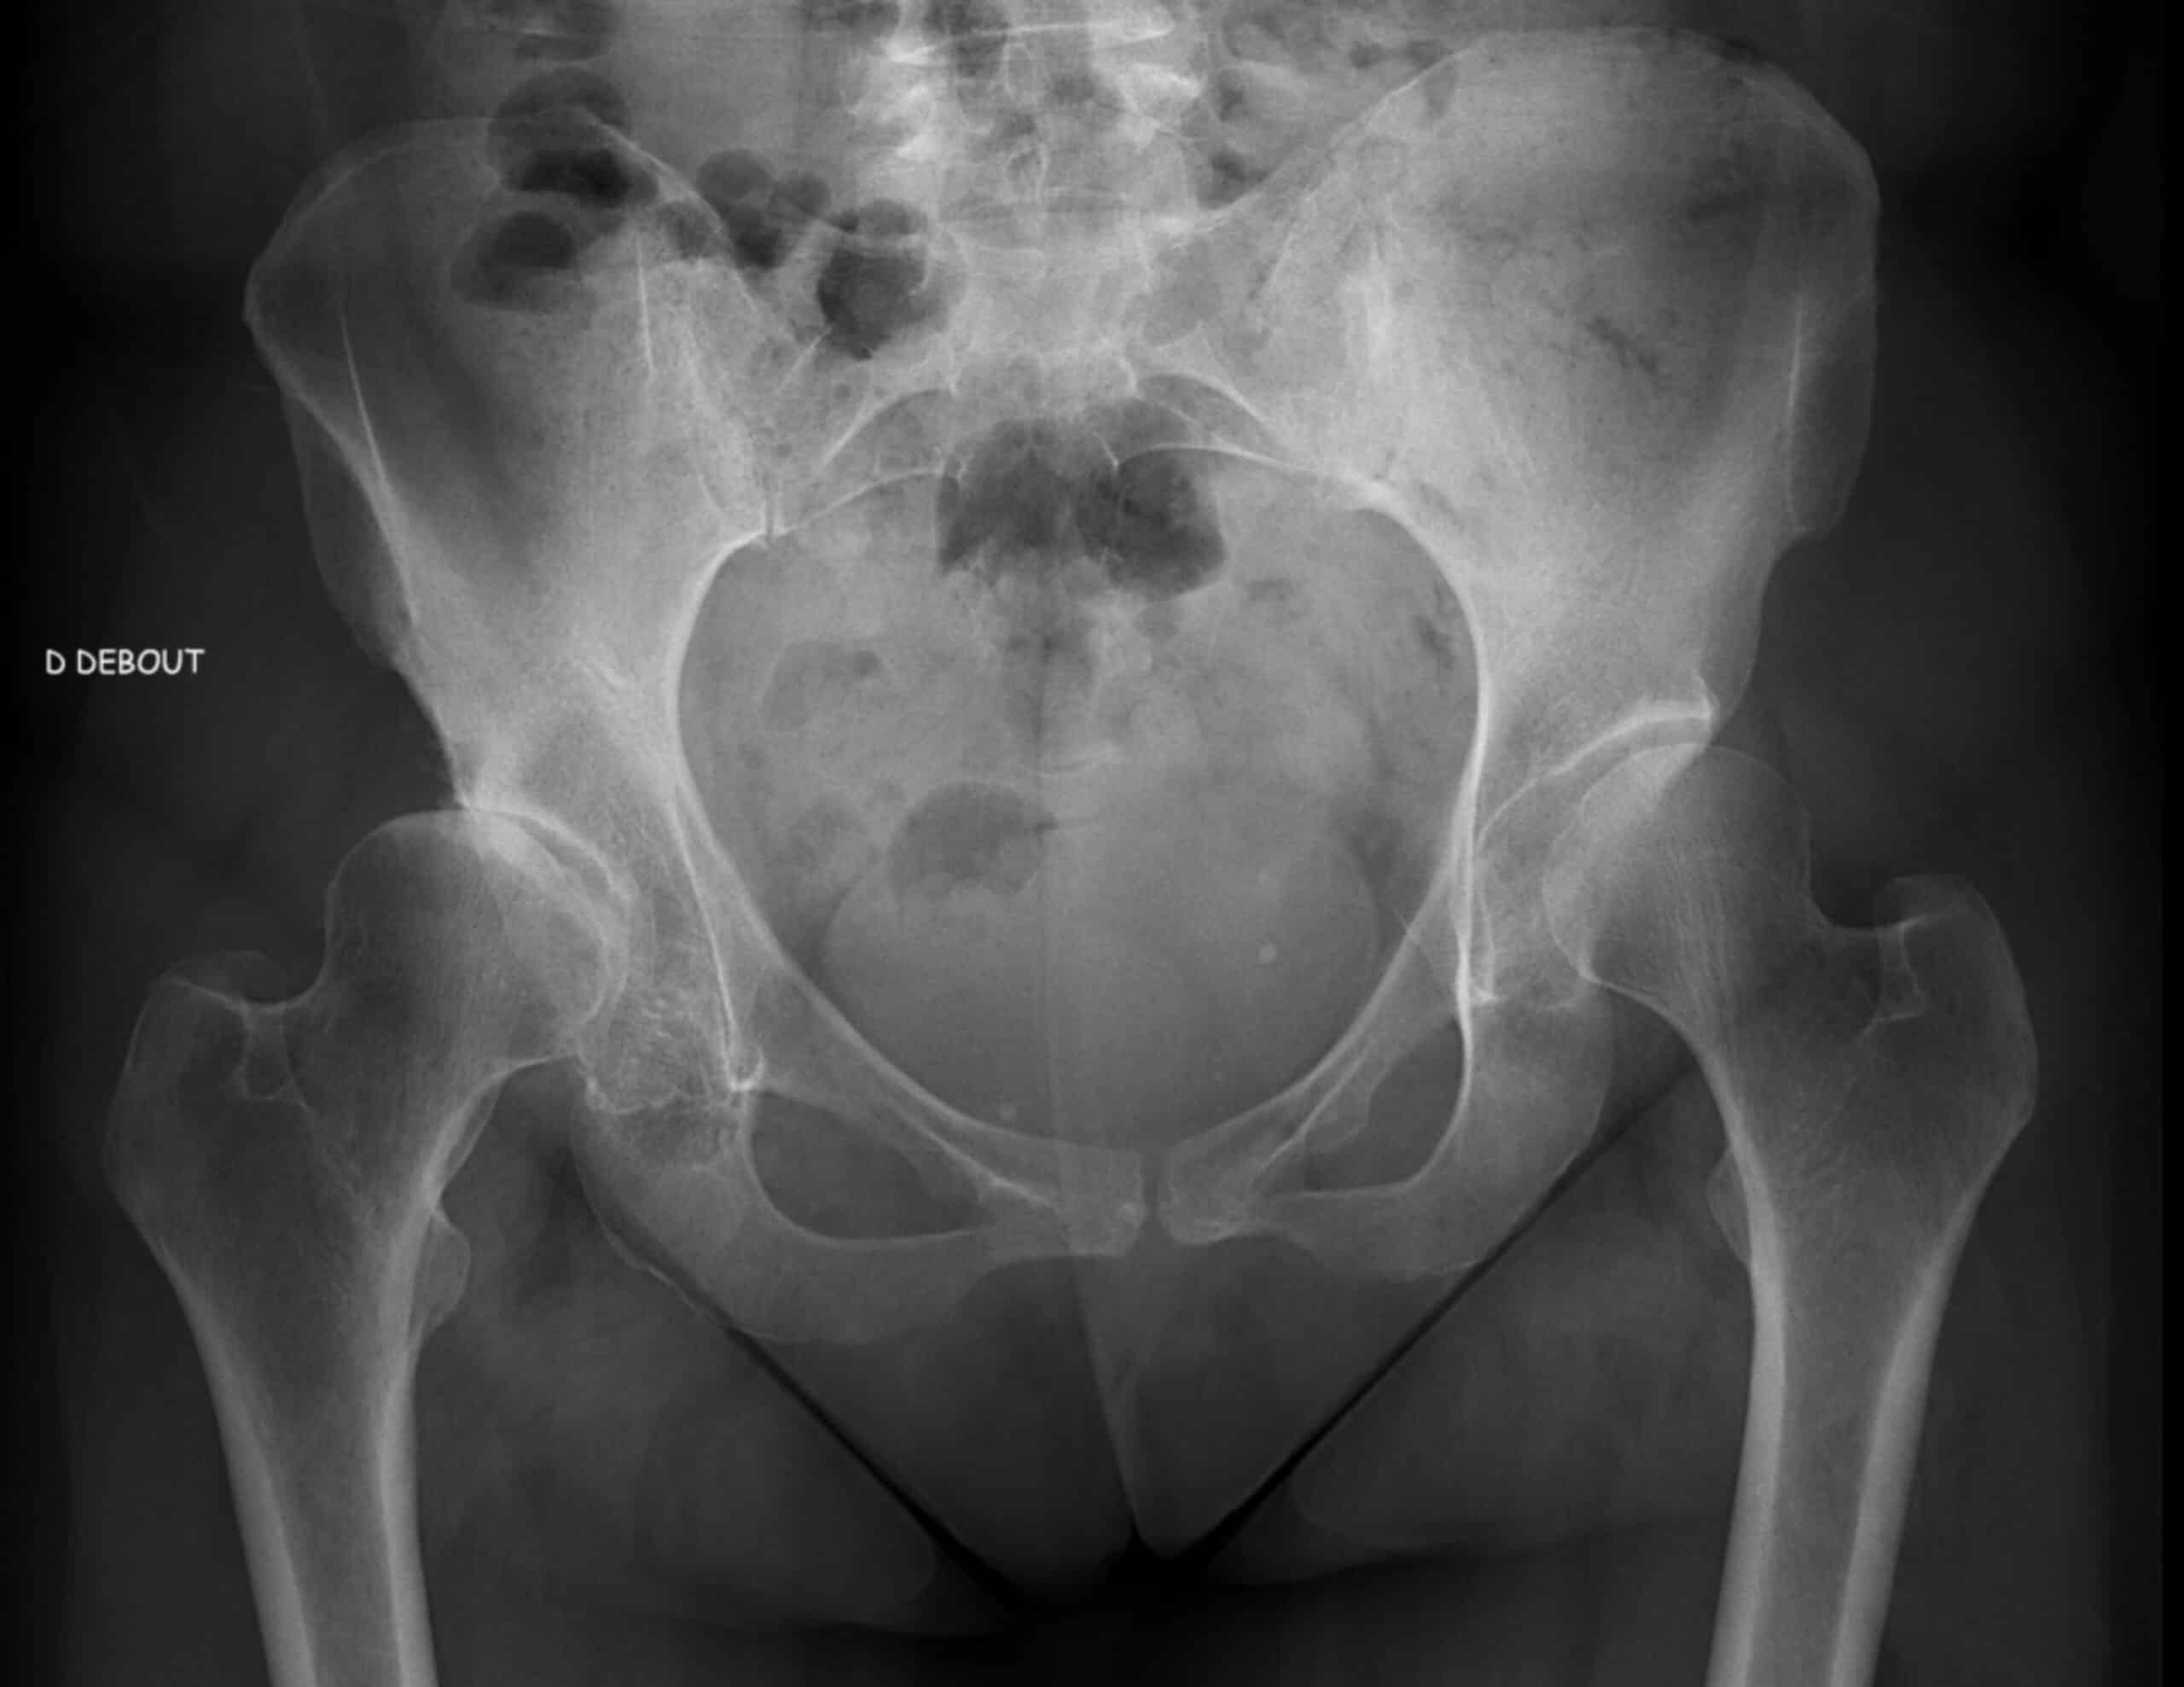

• Radiographie du bassin : C’est l’outil de diagnostic le plus courant. Elle permet de visualiser l’anatomie osseuse et d’évaluer la profondeur du cotyle ainsi que le positionnement de la tête fémorale